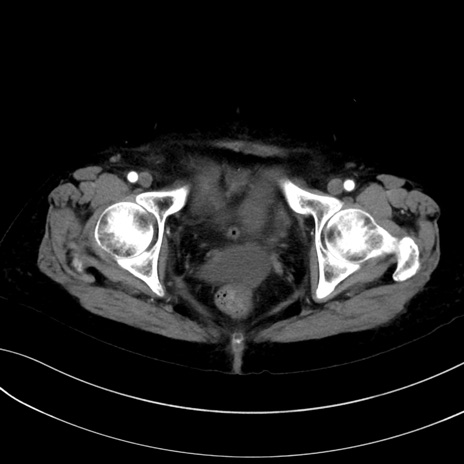

症例13 CT(横断像)1日半後